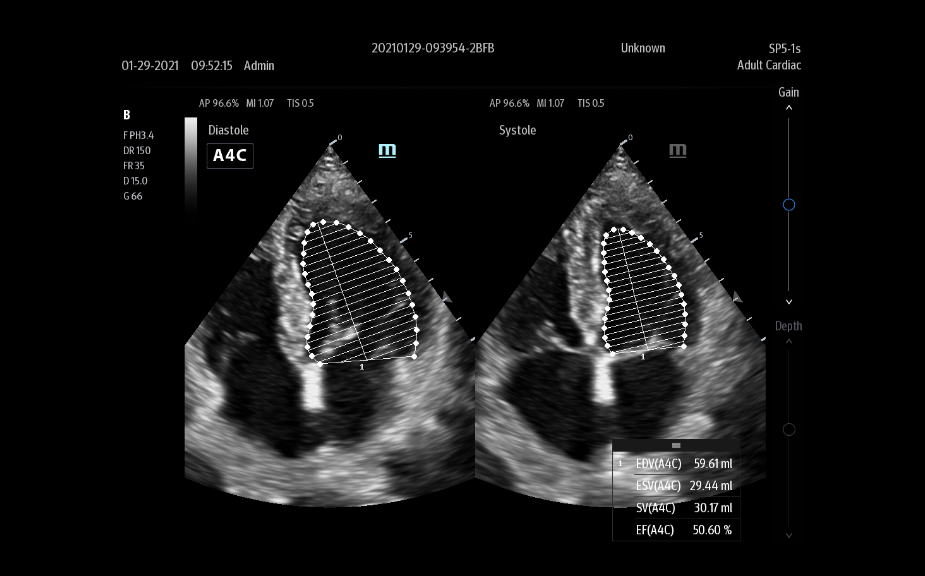

L'├®chographe TE9 a ├®t├® con?u pour faciliter les soins et ├®tendre les capacit├®s d'imagerie pour lŌĆÖanesth├®sie, les urgences et les soins intensifs. Gr?ce ├Ā ses fonctions avanc├®es, son grand ├®cran tactile et sa technologie d'imagerie sup├®rieure, l'├®chographe TE9 permet d'am├®liorer l'efficacit├® clinique et dŌĆÖassurer un diagnostic en toute confiance. Gr?ce ├Ā des outils dŌĆÖacquisition et de calculs automatiques, les soignants peuvent obtenir des mesures rapides et reproductibles dans le cadre d'examens et proc├®dures fiables, m├¬me dans des environnements o├╣ le rythme est soutenu.